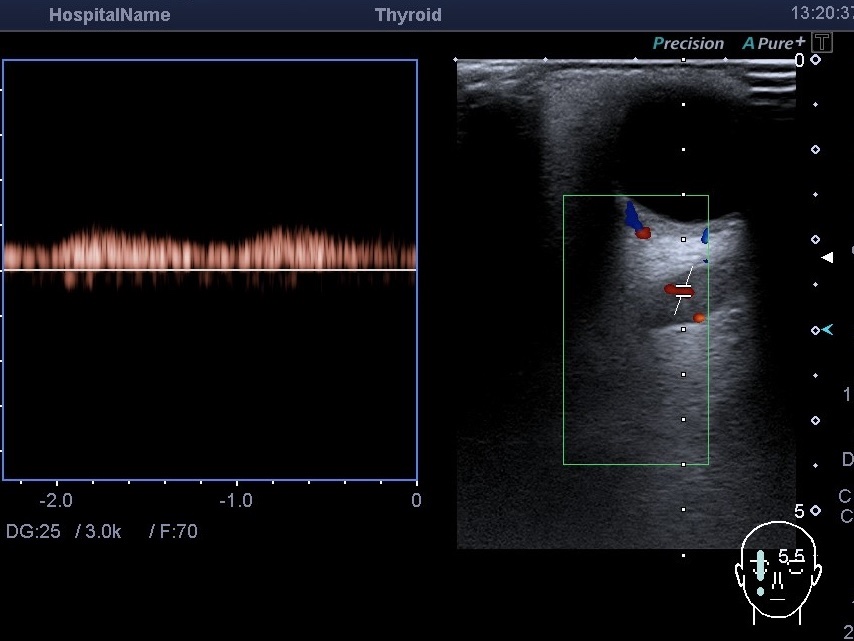

По спектру кровотока мы определяем, венозный это или артериальный кровоток. Однако не всегда вена будет иметь венозный спектр кровотока. Например, бывает так, что артерия и вена имеют соустье (такая аномалия). Каротидно-кавернозное, например. Это когда внутренняя сонная артерия сообщается с кавернозным синусом. При этом на УЗИ мы видим анэхогенную трубчатую структуру за глазом. При включении режима цветового допплера выявленная структура будет расширенной верхней глазной веной. При определении спектра кровотока будет выявлен не венозный, а артериальный спектр кровотока. На сканах представлен случай такой вены, но ещё и с тромбом, который частично растворился (частичная реканализация).